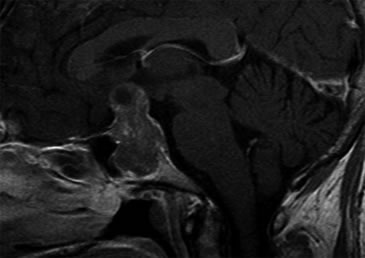

Se realizó una campimetría que evidenció una hemianopsia heterónima temporal. Una RM (Resonancia Magnética) posterior confirmó el hallazgo de adenoma hipofisario de 42 x 34 x 25 mm que realzaba moderadamente con en el contraste paramagnético, con varios quistes de retención glandular (el mayor de aproximadamente 1 cm de diámetro), con extensión supraselar e invasión del seno esfenoidal y seno cavernoso derecho con desplazamiento y compresión del quiasma óptico y del tallo hipofisario (Figuras 1 y 2).

Figura 1. Corte sagital en secuencia T1 con gadolinio.

Figura 2. Corte coronal en secuencia T1 con gadolinio.